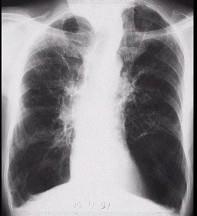

问题 男,65岁,呼吸困难伴胸闷,胸片结果如图,最可能的诊断为 ( )

选项 A.气胸 B.肺结核 C.慢性阻塞性肺疾病 D.肺部感染 E.支气管扩张

答案 C